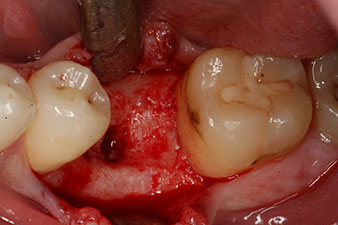

peri-implant bone deficit

Fig. 5: The peri-implant bone deficit must be compensated with autogenous bone chips to restore the peri-implant tissue contour.

This module is an optional extra for the W&H Implantmed and is docked to the implantology motor (see Fig. 11). The dimensionless ISQ value immediately after insertion was 64 orovestibular and 68 mesiodistal (maximum value = 100).

These values could have indicated open healing or even immediate restoration. Due to the insufficient crestal bone volume at the implant, the region was augmented with the bone chips collected during preparation of the implant bed and sutured to exclude saliva.